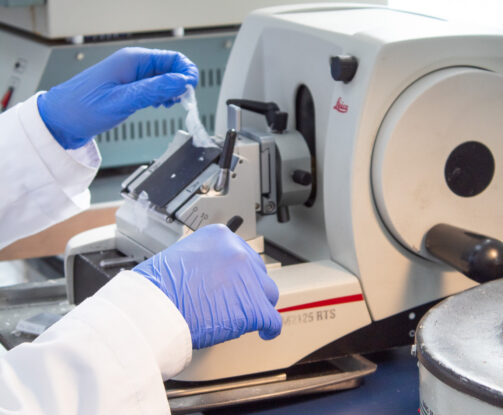

Tecnología Innovadora

En H&E Diagnostics contamos con tecnología de última generación y personal altamente capacitado para el diagnóstico y entrega oportuna de resultados ofreciendo los siguientes servicios especializados: